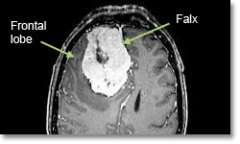

Location - Parafalcine (arising the meningeal layer between the hemispheres of the brain)

Common Symptoms - Seizures, lower extremity weakness, headache, personality changes, dementia, increasing apathy, flattening of affect, unsteadiness, tremor.